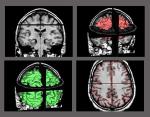

Dans le cerveau, des ensembles de neurones synchronisent leur activité. Les décharges simultanées de ces assemblées de

neurones sont associées à la perception consciente du monde environnant.

...les dernières avancées des neurosciences concernant l’étude du cerveau permettent d’envisager

dans un avenir proche la disparition de toutes les chimères irrationnelles indignes d’un vrai

civilisé. Dieu, transcendance, esprit, amour…, tout ça n’est que le fruit de sécrétions

hormonales et de rouages neuronaux. Seuls des fous, des fanatiques, des arriérés primitifs et

des rêveurs complaisants peuvent encore croire sérieusement qu’il existe d’autres réalités que

celles qu’éclaireront les neurosciences sous la lame de leurs scalpels et les feux des imageries

magnétiques.